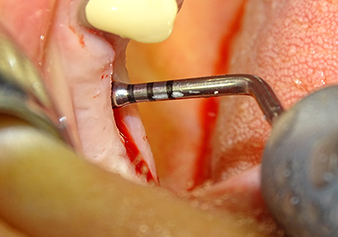

Lo strumento I2A (diametro 2,0 mm) è stato quindi impiegato per perforare il pavimento sinusale in modo graduale e su superfici molto ridotte. Tale metodo piezochirurgico previene il danneggiamento della membrana di Schneider. Durante l'utilizzo di Z25P, la membrana risultava già essere leggermente sollevata dal fluido di raffreddamento fornito attraverso la punta dello strumento (Fig. 3). La quantità di fluido di raffreddamento presente era solo del 50% per evitare che la sede dell'impianto registrasse un'elevata pressione.

Preparazione e accrescimento della sede dell'impianto

Dopo un controllo intermedio (Fig. 4) è stata eseguita un'ulteriore fase di preparazione (Fig. 5). Lo strumento idraulico Z35P è stato utilizzato in un secondo momento per sollevare la membrana sino alla posizione desiderata (Fig. 6 e 7). In seguito alla suddetta operazione, si è proceduto ad una ulteriore preparazione piezochirurgica della sede dell'impianto conclusasi con l'applicazione della fresa e della fresa a spallamento sul diametro dell'impianto di 4,8 mm. Il materiale di rinforzo (dimensione delle particelle di ca. 0,8 - 1,6 mm) è stato introdotto sotto la membrana di Schneider prima che venisse inserito l'impianto (Fig. 8).